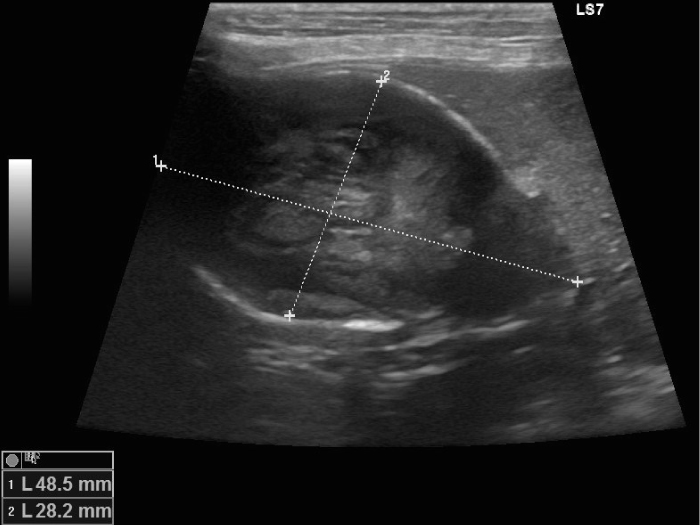

犬 胆嚢粘液嚢腫と胆管にSLUDGEを認める。閉塞の危険性があり胆嚢摘出と胆管洗浄を実施。 無事に何事もなく終了。元気に退院。

胆嚢粘液嚢腫の場合、エコー検査では放射状に胆泥が胆嚢壁に付着したキウイフルーツ状の所見が見られます。

エコーで胆嚢炎と胆嚢粘液嚢腫であることを確認し、破裂の危険性 を考えて腹腔鏡下胆嚢摘出術を実施することになりました。